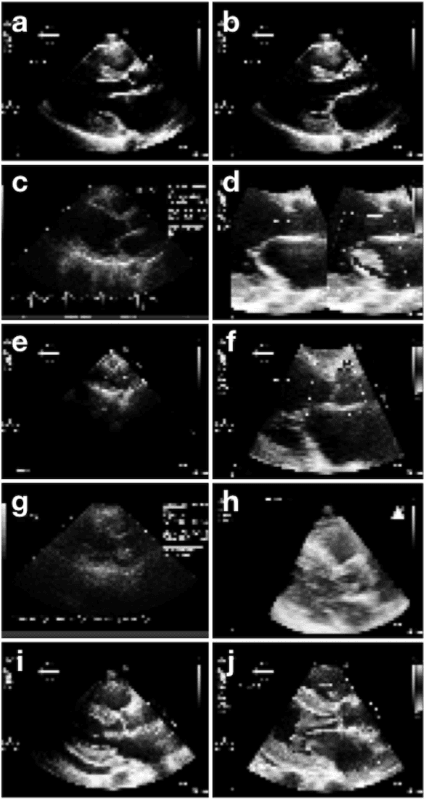

Echocardiography is essential to modern cardiology. However, human interpretation limits high throughput analysis, limiting echocardiography from reaching its full clinical and research potential for precision medicine. Deep learning is a cutting-edge machine-learning technique that has been useful in analyzing medical images but has not yet been widely applied to echocardiography, partly due to the complexity of echocardiograms' multi view, multi modality format. The essential first step toward comprehensive computer assisted echocardiographic interpretation is determining whether computers can learn to recognize standard views. To this end, we anonymized 834,267 transthoracic echocardiogram (TTE) images from 267 patients (20 to 96 years, 51 percent female, 26 percent obese) seen between 2000 and 2017 and labeled them according to standard views. Images covered a range of real world clinical variation. We built a multilayer convolutional neural network and used supervised learning to simultaneously classify 15 standard views. Eighty percent of data used was randomly chosen for training and 20 percent reserved for validation and testing on never seen echocardiograms. Using multiple images from each clip, the model classified among 12 video views with 97.8 percent overall test accuracy without overfitting. Even on single low resolution images, test accuracy among 15 views was 91.7 percent versus 70.2 to 83.5 percent for board-certified echocardiographers. Confusional matrices, occlusion experiments, and saliency mapping showed that the model finds recognizable similarities among related views and classifies using clinically relevant image features. In conclusion, deep neural networks can classify essential echocardiographic views simultaneously and with high accuracy. Our results provide a foundation for more complex deep learning assisted echocardiographic interpretation.